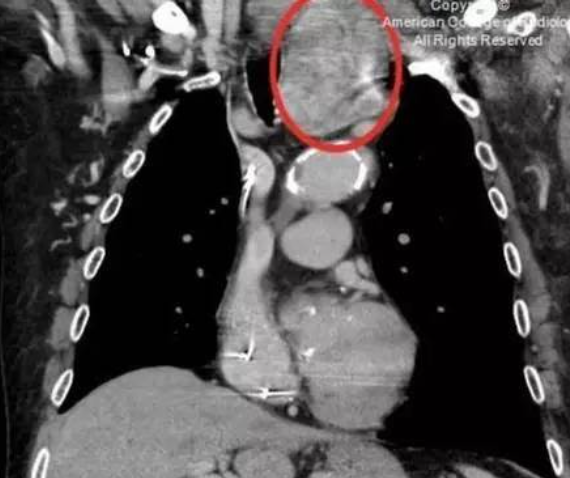

图1胸腺瘤A;图2胸腺瘤AB;图3胸腺瘤B;图4胸腺癌

1.胸腺瘤

胸腺瘤是前纵隔肿瘤最常见的原发性肿瘤,约占50%。

部位:前纵隔中部偏上。

形状:圆形或分叶状实性肿块。

密度:多均匀,可有坏死、钙化。

边缘:良性清楚,病变周围脂肪间隙存在;恶性不清,病变周围脂肪间隙,消失,胸腔及心包可有积液。

增强扫描:实性部分中等强化,坏死区不强化。

组织学分型:A型和AB型为良性肿瘤,B1型为低度恶性,B2型为中度恶性,B3型与胸腺癌均为高度恶性,侵袭性强。